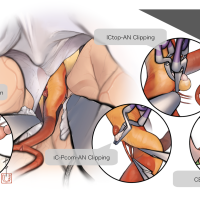

FEN2022シリーズ